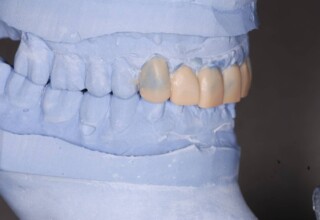

Οι όψεις πορσελάνης είναι ο καλύτερος τρόπος αντιμετώπισης αισθητικών προβλημάτων στην πρόσθια περιοχή του στόματος. Συνδυάζουν συντηρητική αφαίρεση οδοντικής ουσίας και πολύ υψηλή αισθητική απόδοση. Στο παρακάτω εκτεταμένο περιστατικό υπήρχαν: παλαιά σφραγίσματα, δυσχρωμίες, κακό σχήμα και μήκος δοντιών, κακή αναλογία δοντιών-ούλων. Έγινε προσεκτικός εργαστηριακός σχεδιασμός σε εκμαγεία απ’όπου προέκυψαν προσωρινές όψεις που τοποθετήθηκαν στο στόμα για δοκιμή και διορθώσεις. Όταν οριστικοποιήθηκαν οι μετατροπές, οι προσωρινές χρησιμοποιήθηκαν σαν οδηγός για τις μόνιμες. Οι πέντε μόνιμες όψεις πορσελάνης που κατασκευάστηκαν για τα πέντε πρόσθια δόντια της άνω απεκατέστησαν σχεδόν άψογα την αισθητική εμφάνιση της ασθενούς.

Εκτεταμένη αποκατάσταση με στεφάνες(θήκες) σχεδόν σε όλα τα δόντια λόγω εκτεταμένων αποτριβών, παλαιών αποκαταστάσεων, οπισθίων απονευρώσεων και αισθητικών προβλημάτων. Ο ασθενής(60 ετών) παρουσίαζε έντονο βρυγμό (τρίξιμο δοντιών) που δεν είχε αντιμετωπίσει ποτέ, με αποτέλεσμα μεγάλες αποτριβές που απειλούσαν την ακεραιότητα των οπισθίων δοντιών. Οι ανασυστάσεις(σφραγίσματα) των δοντιών έγιναν κυρίως με συγκολλούμενα ρητινώδη υλικά και τρεις χυτούς άξονες ψευδοκολοβώματα. Τοποθετήθηκαν προσωρινές στεφάνες όπου εκτιμήθηκε το επιθυμητό μέγεθος, το σχήμα και η θέση των δοντιών πριν κατασκευαστούν οι τελικές μόνιμες στεφάνες.

Χρησιμοποιήθηκαν παλαιές χαμογελαστές φωτογραφίες της ασθενούς γιατί είχε χαθεί τελείως το φυσικό σχήμα των δοντιών εξαιτίας των πολλαπλών προσθετικών προσπαθειών που είχαν γίνει στο παρελθόν. Μεταφέρθηκε στην προσωρινή γέφυρα η σχέση των φυσικών δοντιών μεταξύ τους άλλα και με τα χείλη. Δοκιμάστηκε η φώνηση και η μάσηση με δυο διαφορετικές προσωρινές άνω γέφυρες και εκτιμήθηκε η αισθητική απόδοση τους. Αφού επιτεύχθηκαν σε βαθμό ικανοποιητικό η φώνηση και η αισθητική εμφάνιση της οδοντοφυΐας, η προσωρινή αποκατάσταση χρησιμοποιήθηκε ως οδηγός για την τελική.